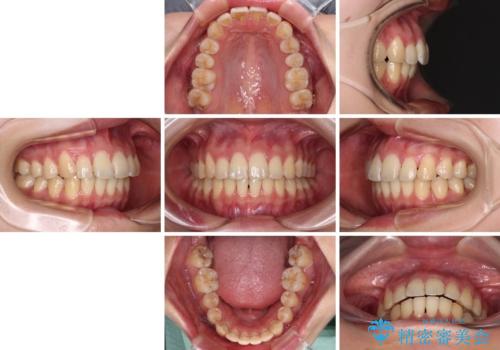

奥歯の咬み合わせはしっかりと改善され、前歯の突出感も改善されました。

- 1年5ヶ月

- 治療回数

- 10-30回